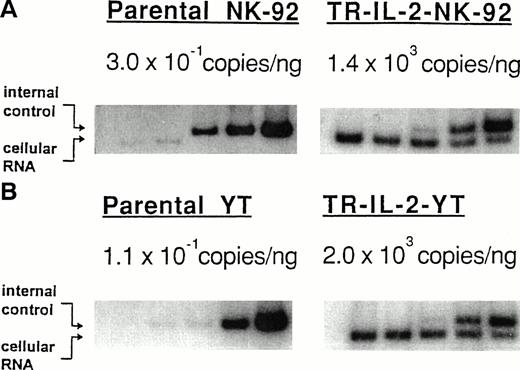

Expression of IL-2Rs and other markers in parental and transduced NK cell lines.

The ability to produce and secrete IL-2 could lead to changes in IL-2R expression on transduced NK cells. Therefore, surface expression of IL-2R α, β, and γ was measured by flow cytometry in the parental and IL-2 gene–transduced and selected NK cell lines. With P-NK-92 cells, flow cytometry was performed after 48 hours' incubation in the absence of exogenous IL-2. The flow cytometric data shown in Fig6 indicate that TR-IL-2-NK-92 cells have lower surface expression of IL-2R α and β than P-NK-92 cells. Expression of the γ chain was also decreased in transduced NK-92 cells relative to P-NK-92 cells (data not shown). Similarly, TR-IL-2-YT cells have lower cell surface expression of IL-2R β and γ chains than P-YT cells. YT cells do not express IL-2R α. These patterns of surface expression of IL-2Rs are expected, because transduced NK cells produce IL-2 and thus IL-2Rs are likely to be occupied by the endogenously produced ligand and internalized or shed from the cell surface.

IL-2R expression on the parental and IL-2 gene–transduced NK cell lines as determined by flow cytometry. Nonpermeabilized or permeabilized cells were stained with the appropriate antibodies for IL-2 α, β, and γ chains and examined by flow cytometry. One representative experiment of 3 performed is shown. (A) NK-92 cells, (B) YT cells.

IL-2R expression on the parental and IL-2 gene–transduced NK cell lines as determined by flow cytometry. Nonpermeabilized or permeabilized cells were stained with the appropriate antibodies for IL-2 α, β, and γ chains and examined by flow cytometry. One representative experiment of 3 performed is shown. (A) NK-92 cells, (B) YT cells.

Intracytoplasmic expression of IL-2R in the IL-2 gene–transduced and selected NK cell lines, as detected by flow cytometry, was also lower than in parental cells (Fig 6). This observation is consistent with a rapid turnover of IL-2R chains in transduced NK cells, which secrete IL-2.